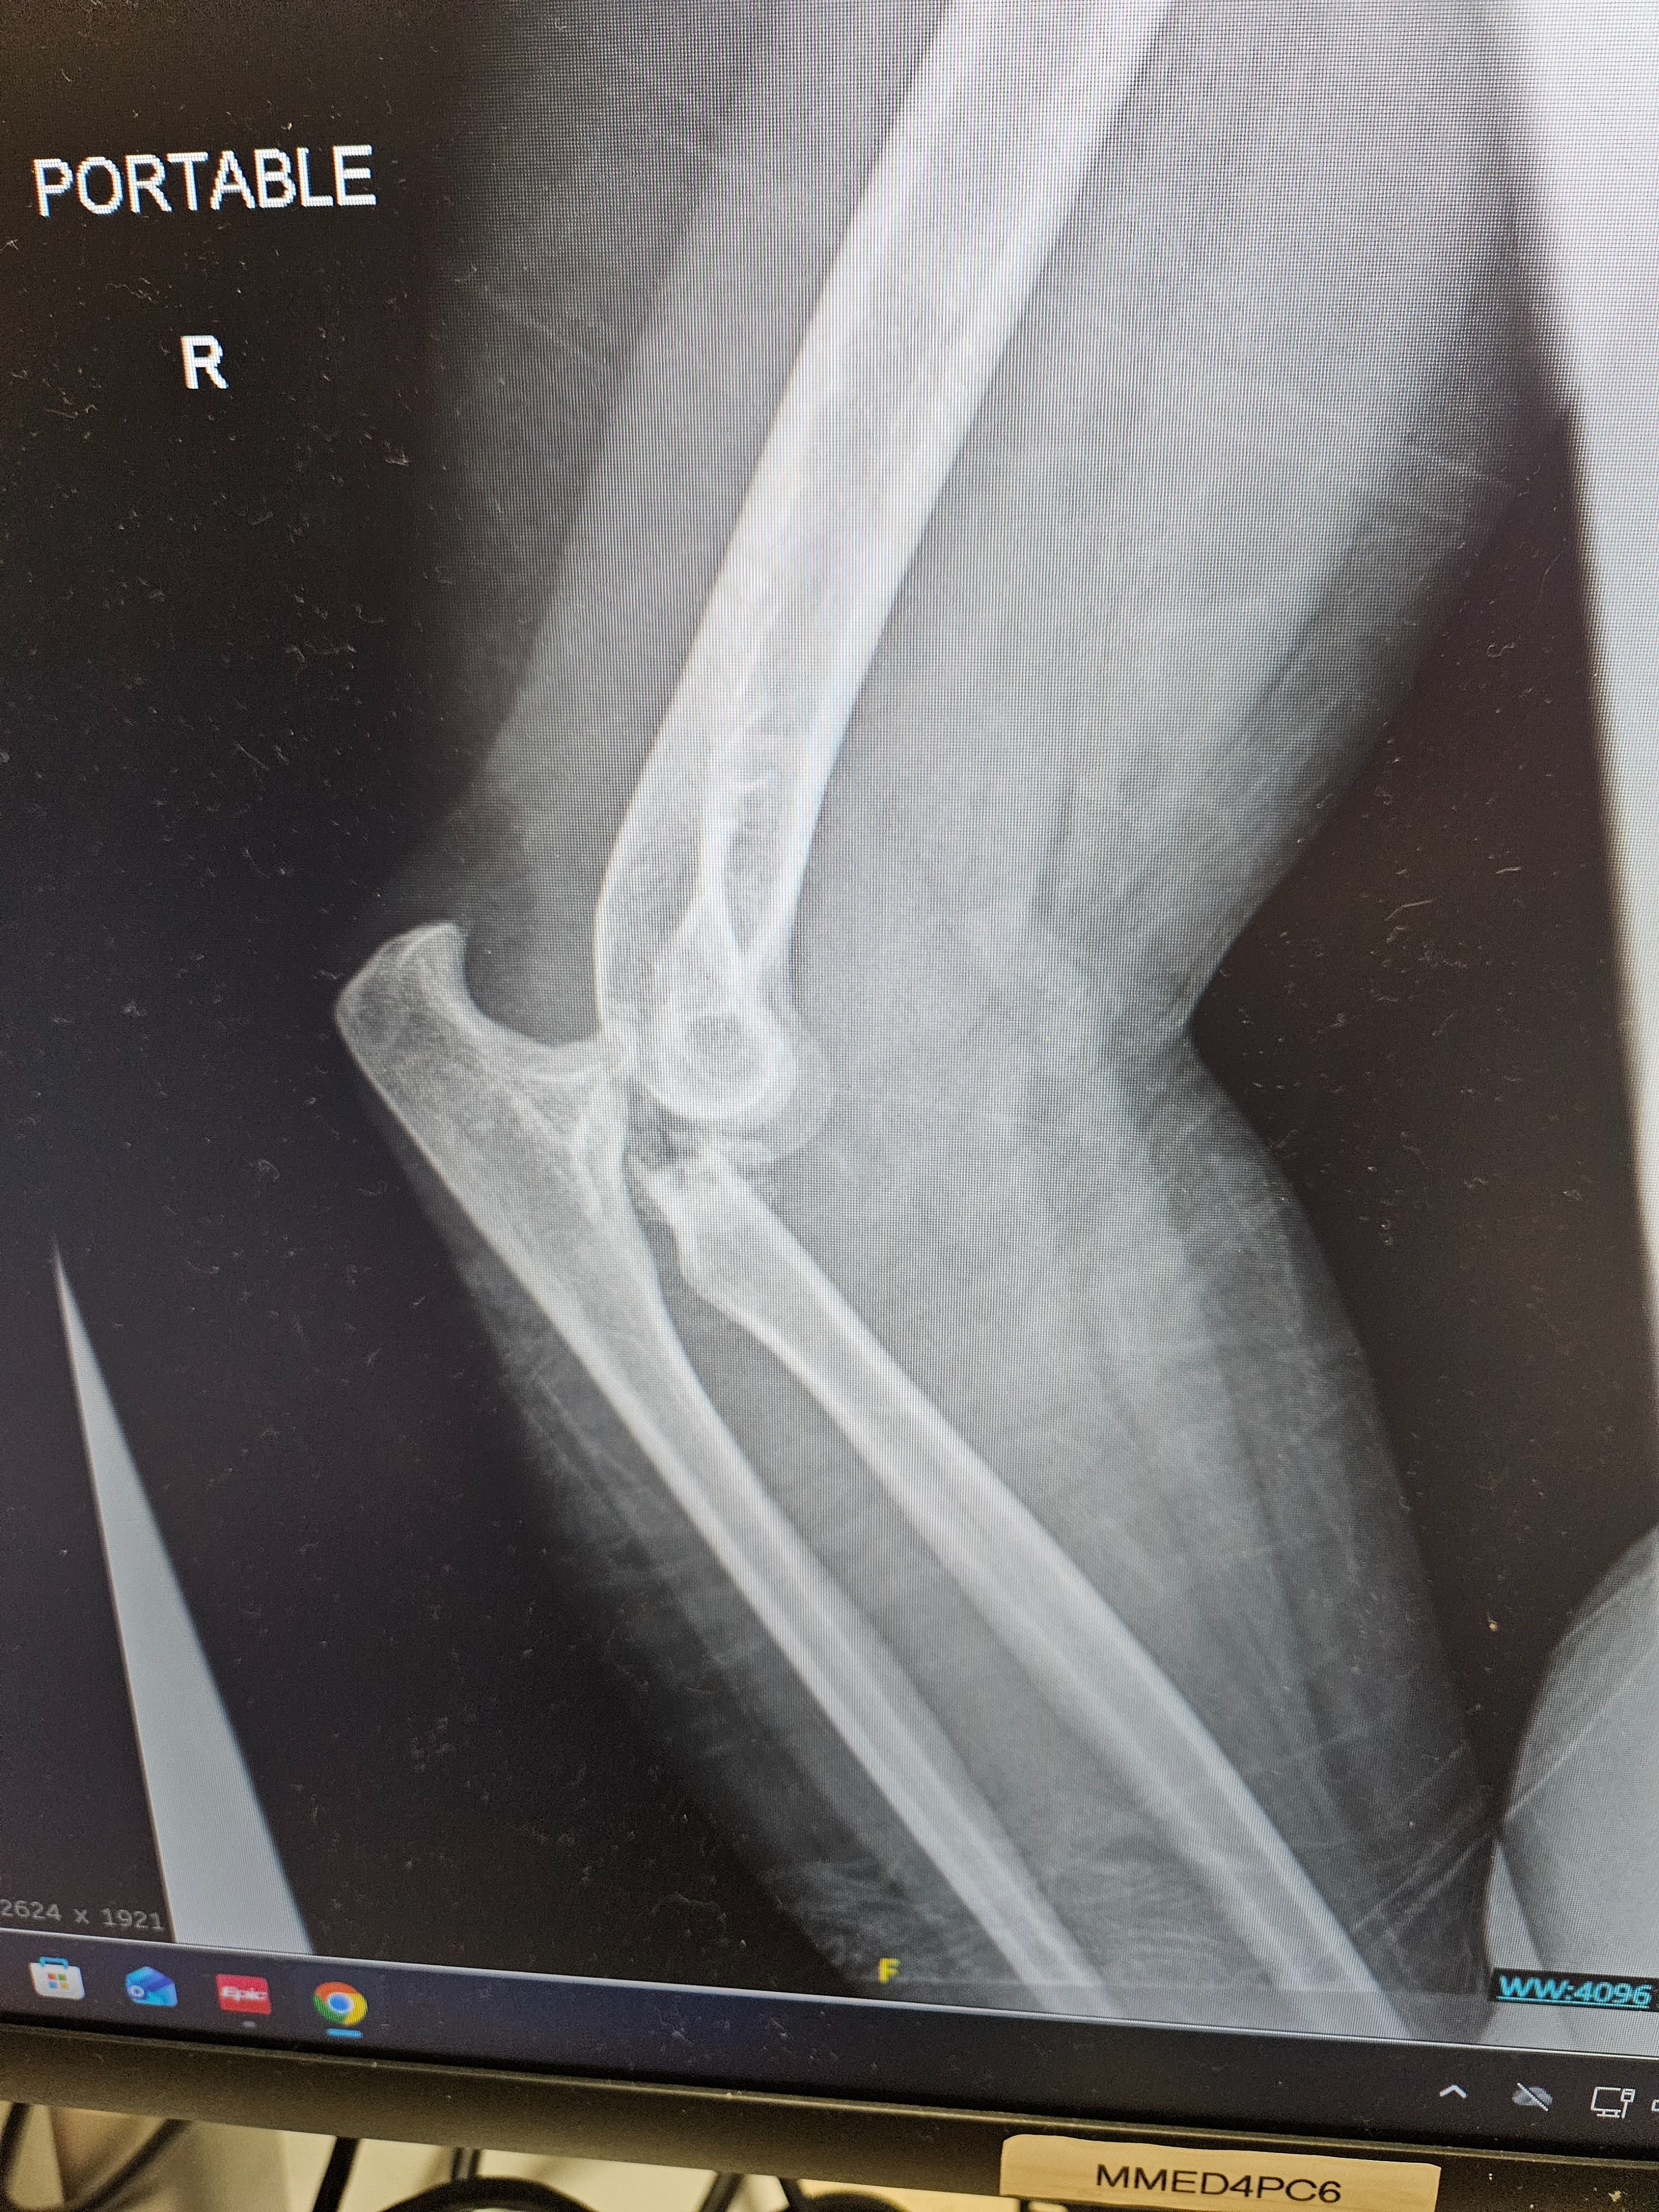

We’re raising funds to support our coworker and friend who recently suffered a serious fall, resulting in dislocated and fractured elbows on both arms. This unexpected injury has left her unable to work for the foreseeable future as she undergoes treatment and recovery.